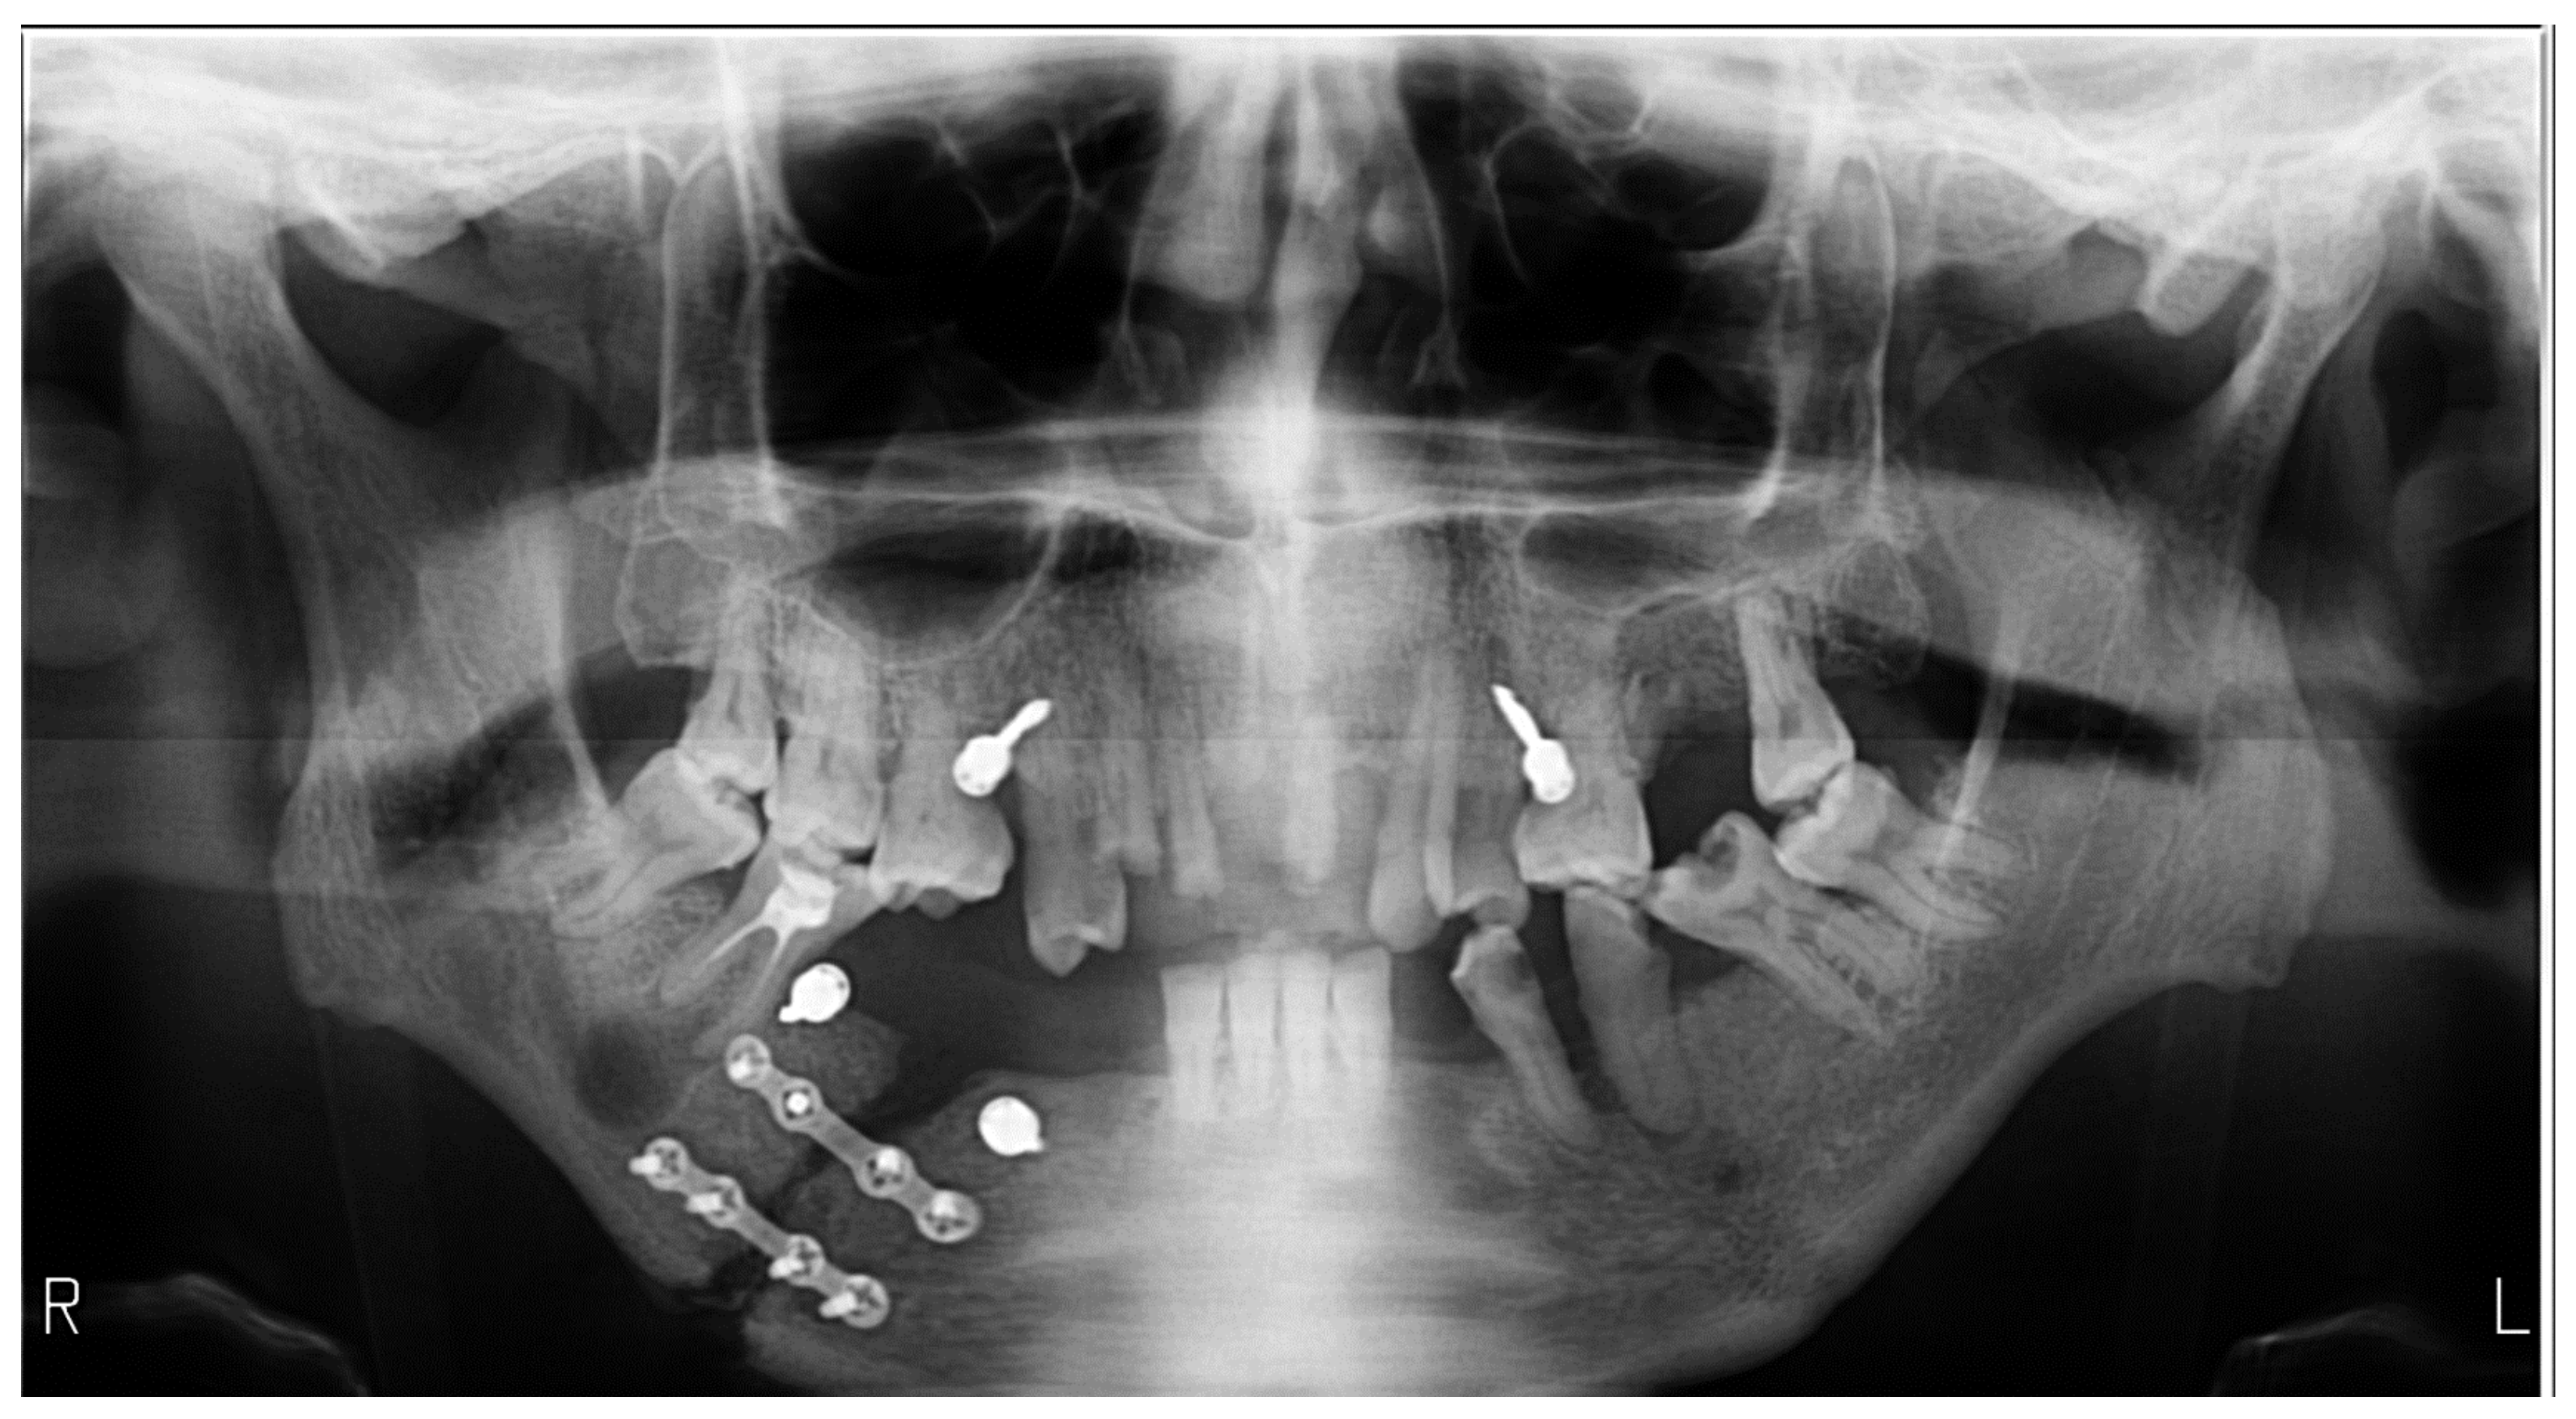

| Radiographs with bimaxillary immobilization errors | 23 | 76.66 | 62.16 | [59.07–88.21] * |